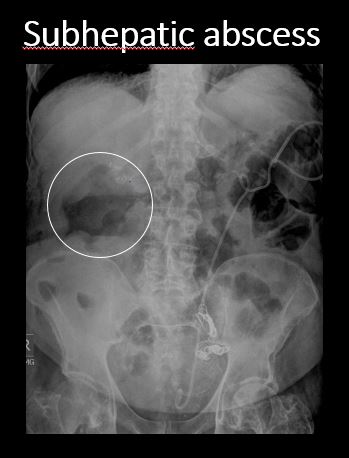

There is a soft tissue mass in the abdomen or pelvis. |

No | NA |

There is retroperitoneal air outlining the right psoas muscle likely from duodenal perforation, from recent endoscopy. There are a few distended loops of small bowel in the mid and lower abdomen.